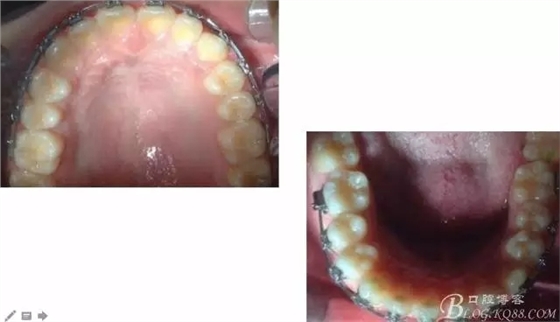

640.webp (3).jpg

640.webp (4).jpg